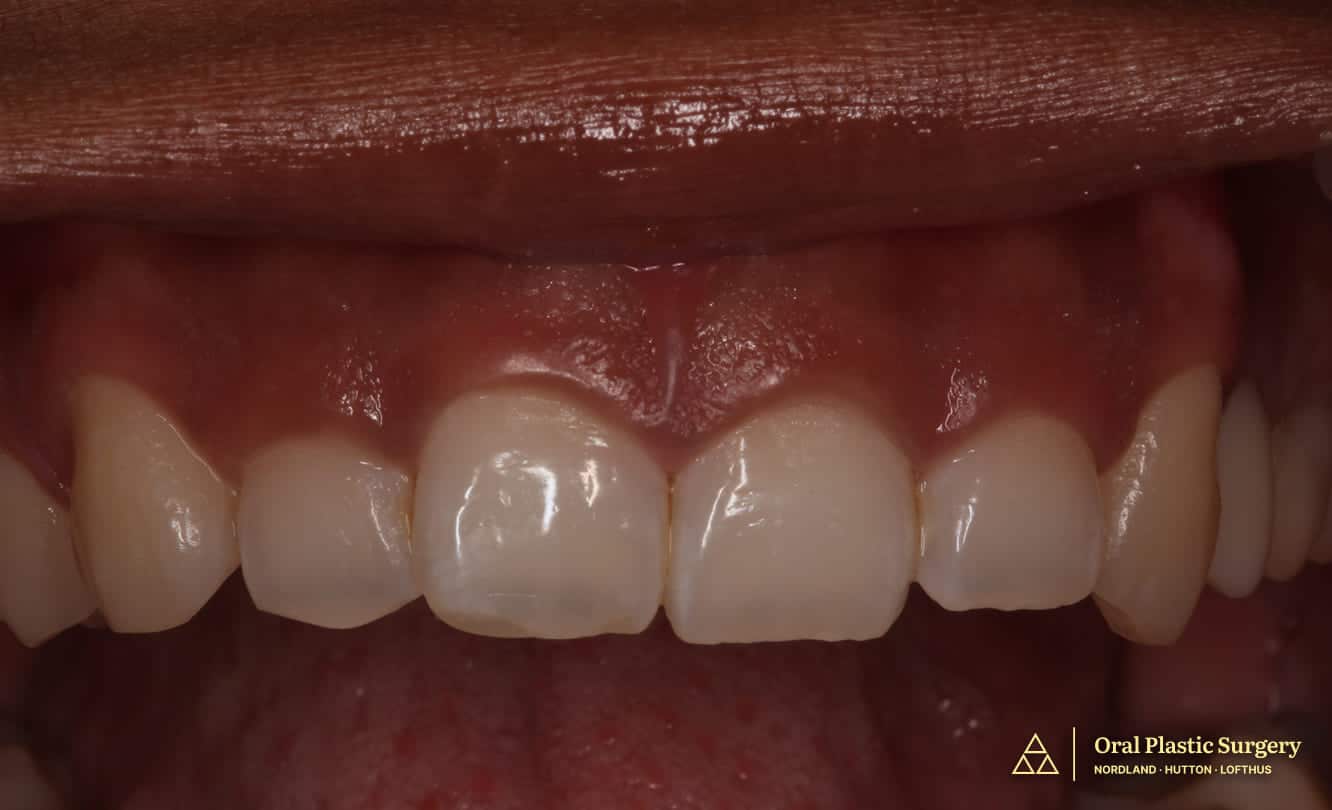

Final post-treatment results demonstrating seamless integration of restored gums and custom restorations following four-month comprehensive treatment.